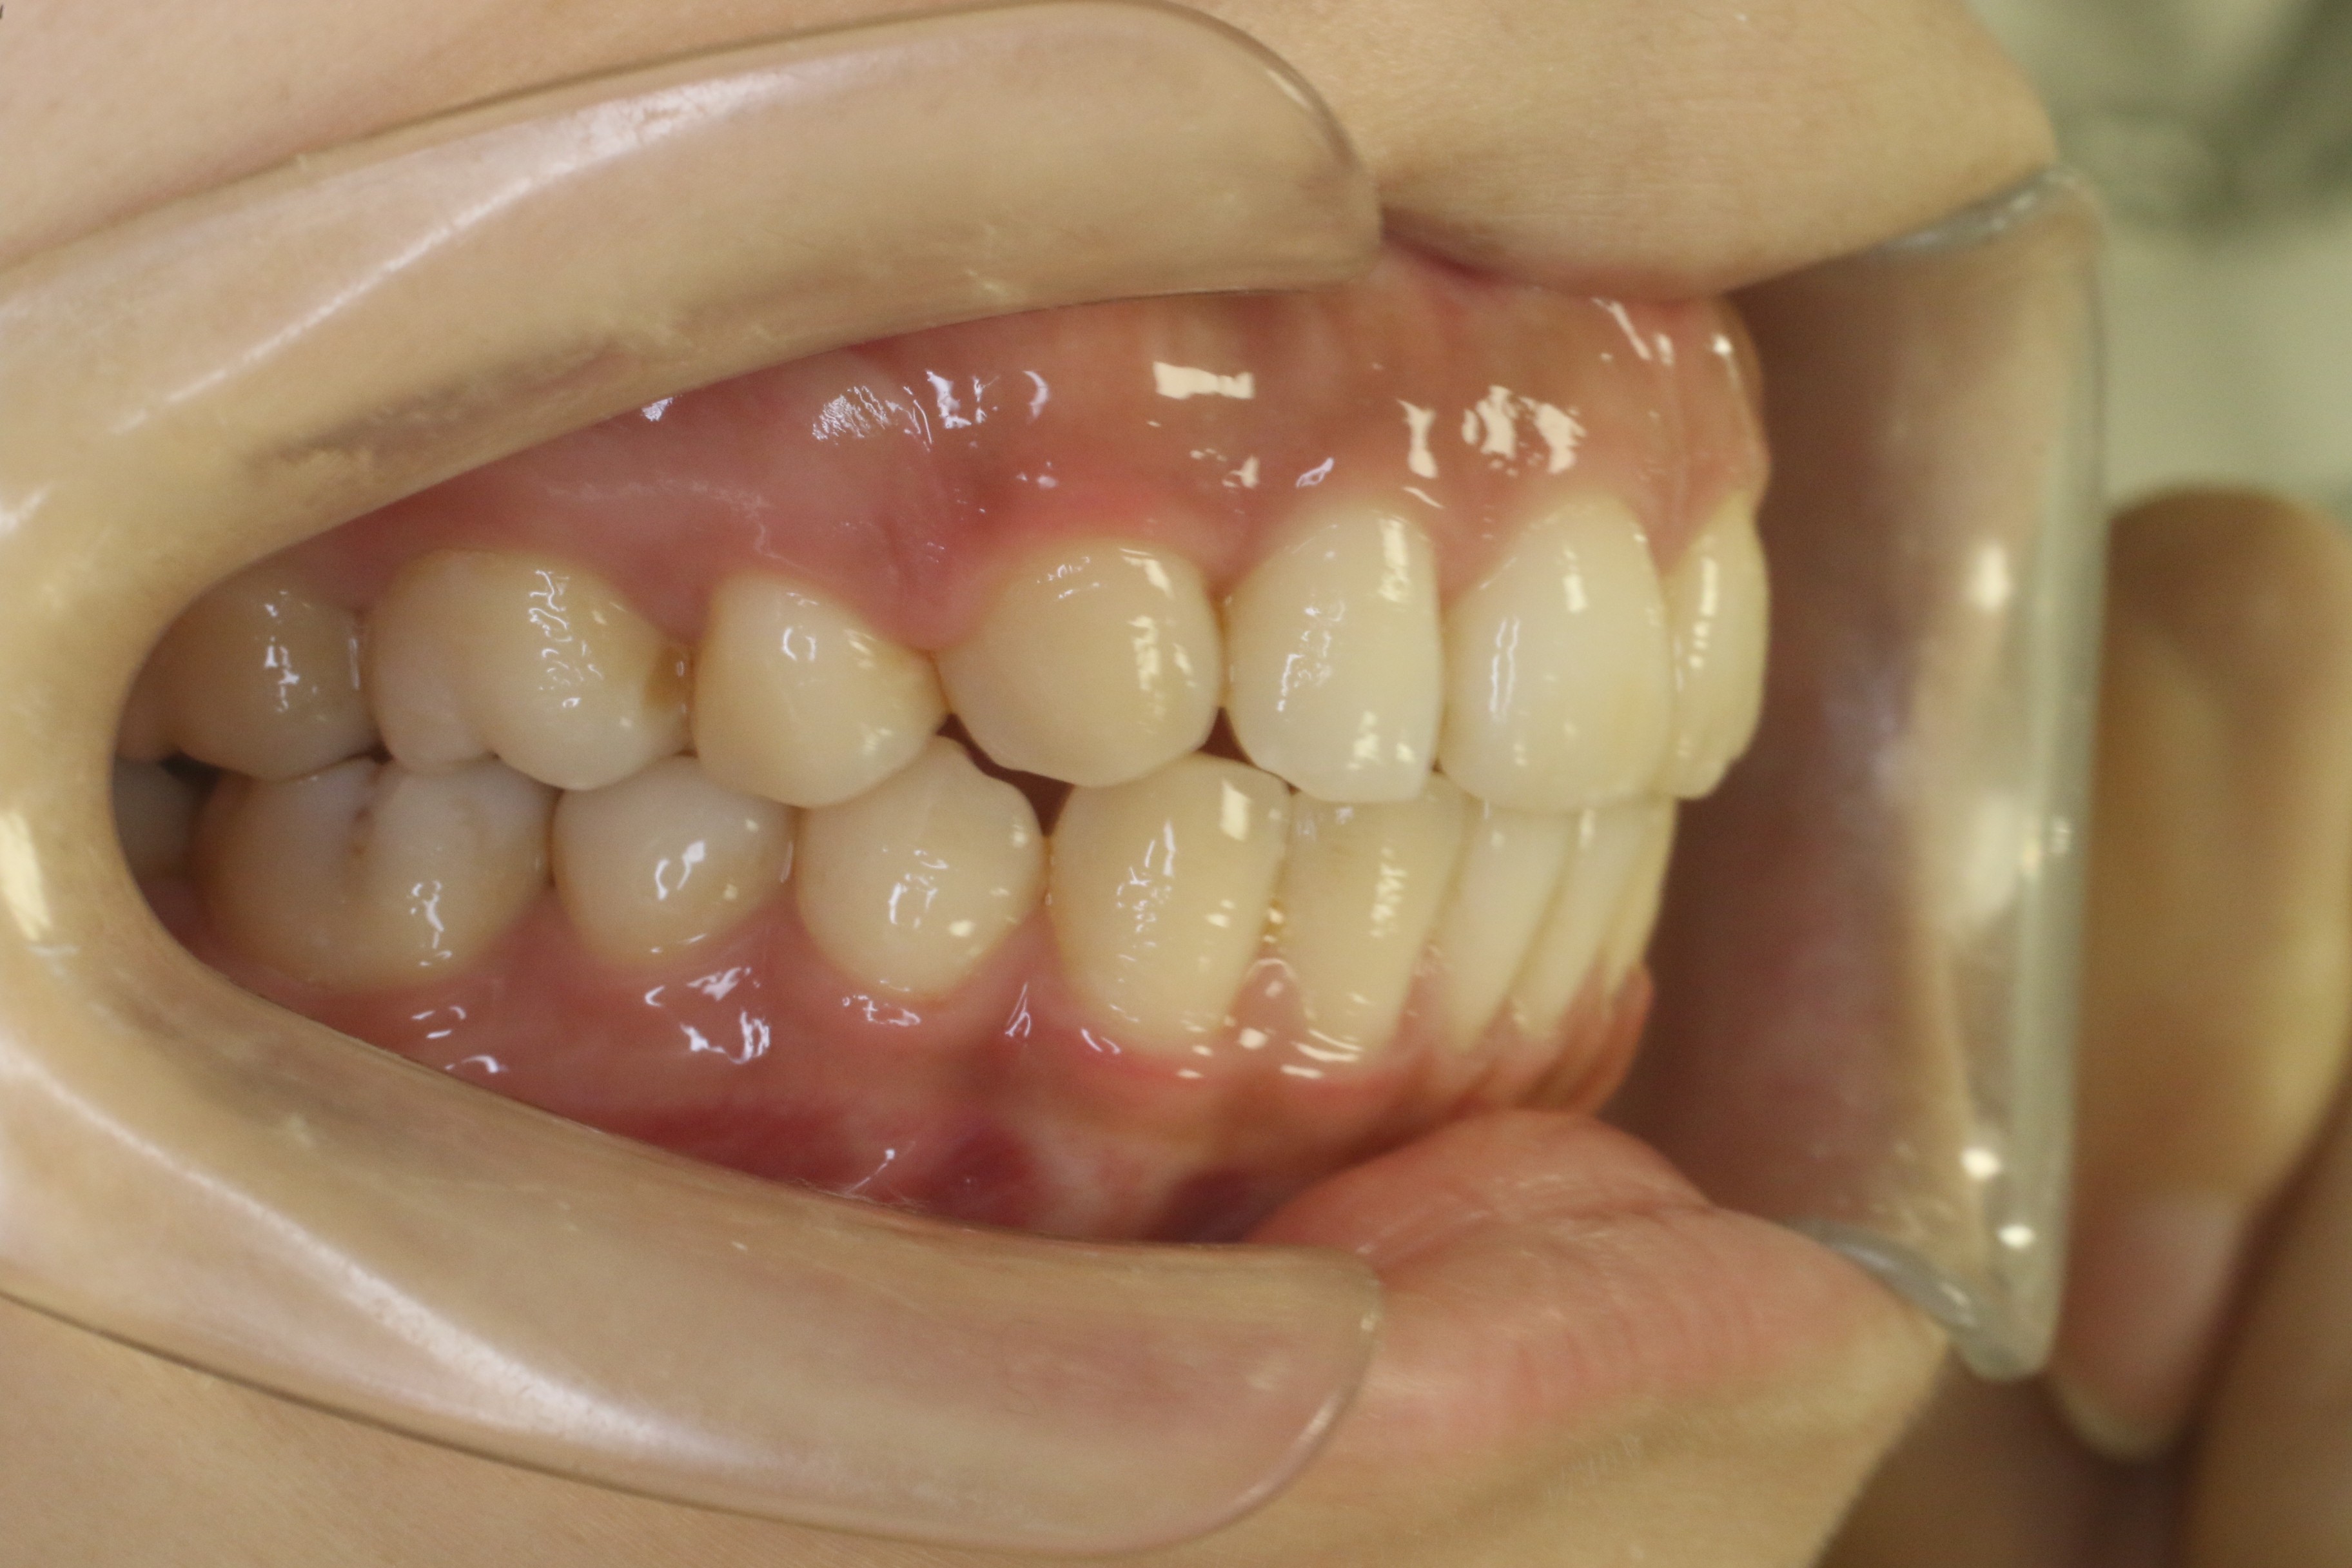

受け口を治したい

年齢層 20代

性別 女性

主訴 【主訴】受け口を治したい 【診断・症状】反対咬合、上下凸凹

治療費用 検査・診断:38,500-/ハーフリンガル矯正治療:1,287,000-(※全て税込)

治療期間 約1年半(20回)

抜歯 無(非抜歯)

矯正の装置 ハーフリンガル矯正

副作用、リスク 歯肉退縮,歯根吸収,疼痛,咬合の違和感,装置の違和感,虫歯,歯肉炎

case17_受け口_before

Before

case17_受け口_after

After